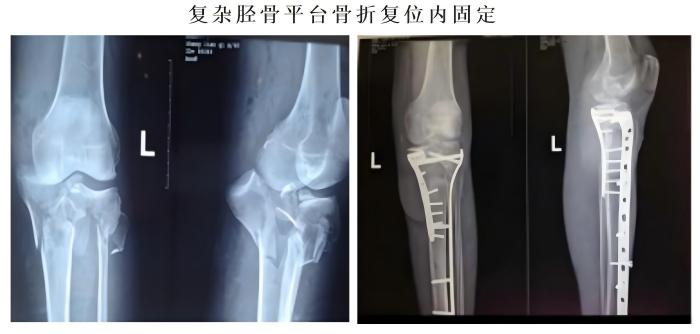

常规开展人体各部位骨折、脱位的修复重建。业务亮点:①伦理片骨科对于复杂胫骨平台的治疗方法获得国际“平台大师”罗从风教授的高度肯定,并将其编入胫骨平台骨折诊疗教程。②伦理片骨科通过Stoppa入路,结合传统入路的精髓,治疗复杂骨盆骨折,并在福建省率先使用骨折微创内支架治疗骨盆前环损伤。③对于四肢长管状骨骨折,伦理片骨科通过几个1-2CM的手术切口,闭合复位骨折,微创插钉,不破坏骨折端软组织及血运。不但减小了手术创伤,还提高了愈合速度。④伦理片骨科于国内首创使用“微创钛揽捆扎固定”,治疗肩锁关节脱位,完美解决传统手术手术创口大,肩关节活动差,内固定撞击等诸多缺点。